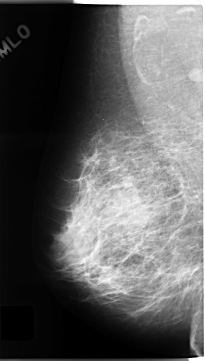

C_0136_1.RIGHT_MLO

LEFT_MLO LINES 4728 PIXELS_PER_LINE 2808 BITS_PER_PIXEL 12 RESOLUTION 50 OVERLAY